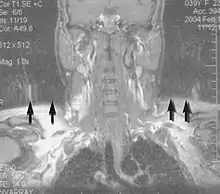

Artifacts

Motion artifact (T1 coronal study of cervical vertebrae)[117]

An MRI artifact is a visual artifact, that is, an anomaly during visual representation. Many different artifacts can occur during magnetic resonance imaging (MRI), some affecting the diagnostic quality, while others may be confused with pathology. Artifacts can be classified as patient-related, signal processing-dependent and hardware (machine)-related.[117]